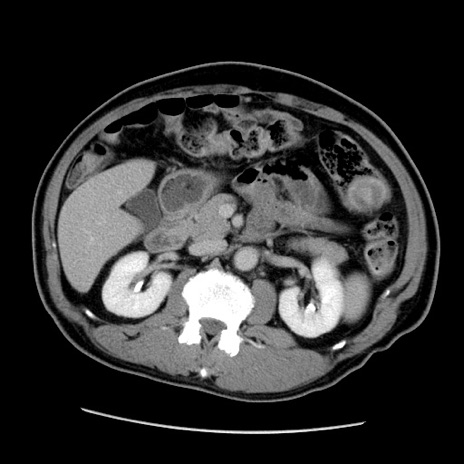

症例22(横断像)

【症例】50歳代男性

【主訴】腹痛

【現病歴】AVMからの被殻出血のため回復期リハ病棟入院中。 本日午後3時頃急に下腹部痛が出現した。

【既往歴】AVM、被殻出血、虫垂炎、高血圧

【身体所見】意識晴明、左半身不全麻痺、会話の理解は良好、36.5°C、腹部:膨隆、全体に板状硬、下腹部正中に圧痛点あり、反跳痛-、筋性防御不明、右下腹部にope scar

【データ】WBC 9400、CRP 0.06